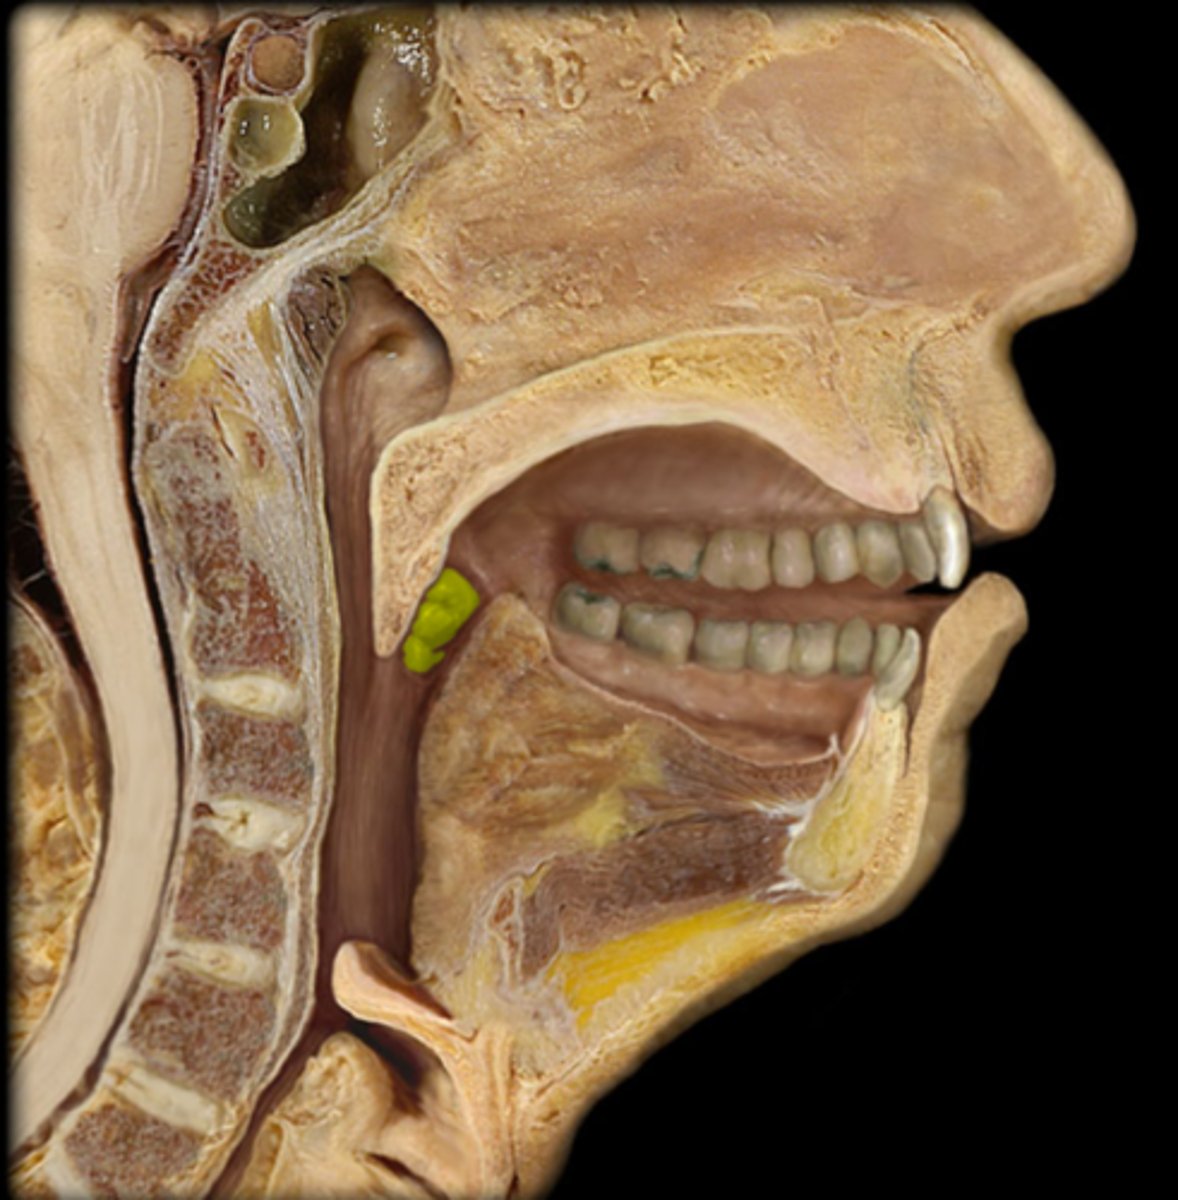

palatine tonsil

2